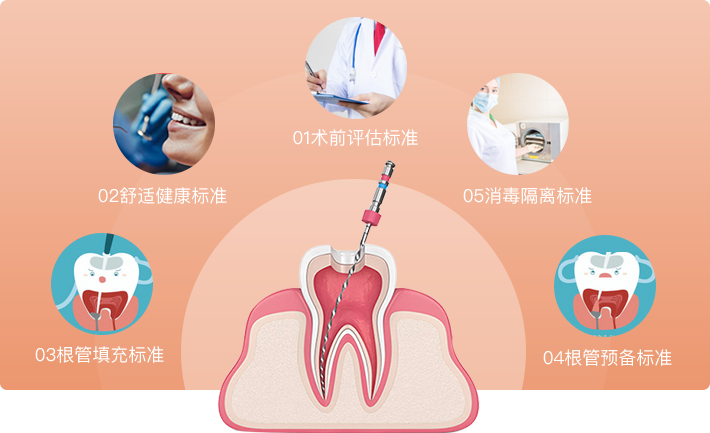

根管治疗严格遵循口腔诊疗标准

TAIKANG BYBO DENTAL

泰康拜博口腔严格按照全国口腔诊疗标准,严格监管消毒与院感管理,不仅采用国外进口优质材料,同时,斥资引入国外诊疗设备,全面加强诊疗的高效性、精准性,打造品质口腔服务体系。